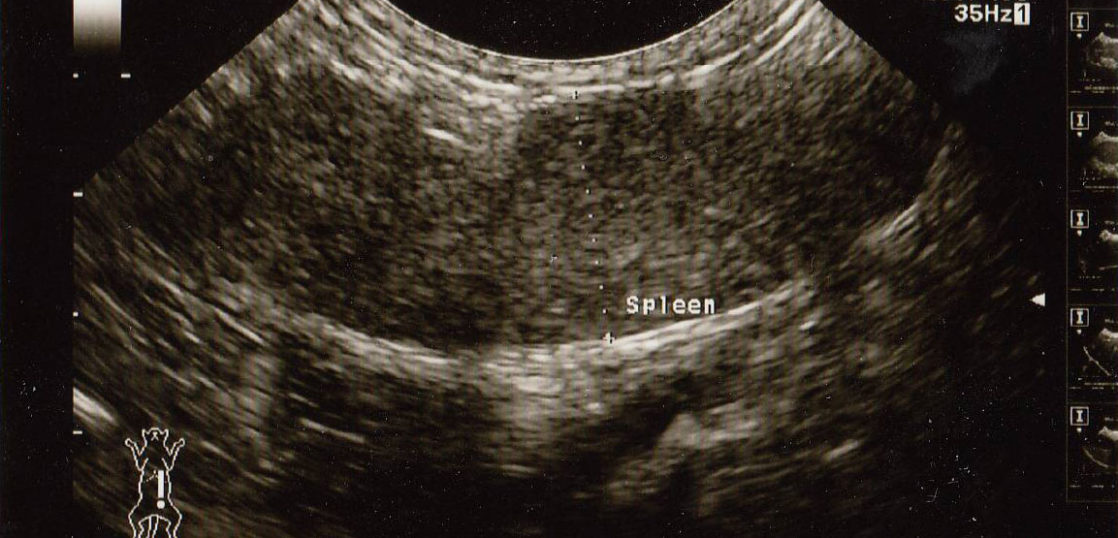

【2017年5月】黄色いラインで囲まれているのが腫瘍です。5㎝大の大きな腫瘍が確認できます。

コルディの服用とオゾン療法を行い3週間後には触診で確認できなくなりエコー検査も行わずに経過を観てきましたが、その後も良好な体調が続いていましたので、悪性リンパ腫の治療を開始して3ヶ月後に腹部エコー検査を行いました。

その結果、エコー画像上で腹部にあった腫瘍は確認できませんでした。